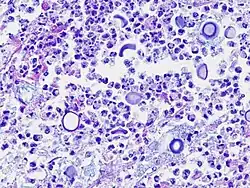

Cryptococcus kann lichtmikroskopisch in einer Tuschefärbung nachgewiesen werden. Charakteristisch sind die sich nicht anfärbenden Polysaccharidkapseln. Für den ungeübten Untersucher können Leukozyten oder Lipidartefakte Cryptococcen vortäuschen. Der Nachweis ist aus Blut und Nervenwasser möglich. Der lichtmikroskopische Test kann bei einer niedrigen Erregerzahl falsch-negativ sein.[8]